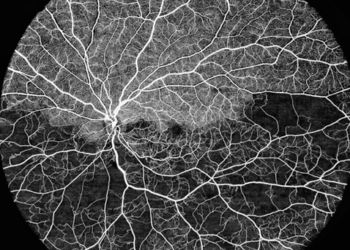

Single scan OCT image from VG-200I

Retina Imaging

Supports high-resolution retinal structure evaluation with broad scan capability for routine and advanced assessment.

• 16 mm maximum retina scan range

• 15 mm × 12 mm maximum 3D scan range